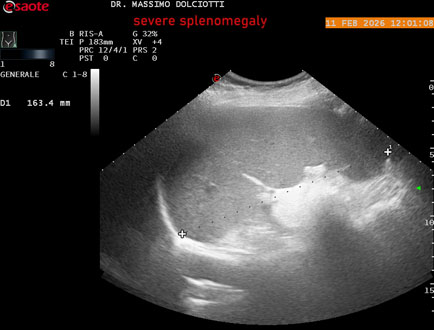

Data inserimento: 18/02/2026

Ecografia del: 11/02/2026

Strumento: Esaote MyLab Eight

Sonda: Conevx Multifrequenza 1-8 MHz

Età Paziente: F 68 anni

Motivazione dell'esame: follow up di splenomegalia.

Commento all'esame: le immagini ed il video documentano la milza con ecostruttura normale e morfovolumetria superiore alla norma, con diametro bipolare di 159 mm (v.n. 70-120 mm) ed area di sezione di 101 centimetri quadri (v.n. < 47 centimetri quadri).

Conclusioni: splenomegalia di severa entità (severe splenomegaly).